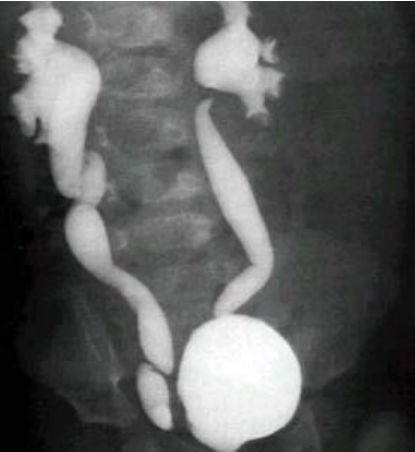

The radiological test shown is called Micturating Cysto-urethrogram - (2 .or voiding cysto-urethrogram (VCUG) (MCUG)

There is reflux of the dye up to the collecting system with cupping of calyces - and tortuosity of the ureter in the right side (Vesico-urethric Reflux [VUR] grade .V)). The left ureter is less severely affected

The patient is slightly hypertensive which means there is residual damage - .from recurrent UTI

For that reason, she needs further investigation such as Renal U/S looking for hydronephrosis and assessing the echogenicity of the kidneys, DTPA for functional assessment of renal function and DMSA to look for renal scar from .previous UTIs

- Name the test?

- Voiding cystourethrogram (VCUG)

- List Findings?

- posterior urethral valve

- dilated ureters

- tortious ureters

- dilated uretric pelvic bilaterally (hydronephrosis)

- Diagnosis?

- VesicoUretral Reflux (VUR)